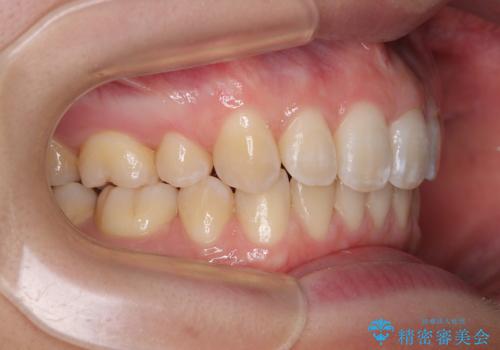

上下歯列の前後位置を見ると、上顎が全体的に前方に位置しており、上顎前歯が前方に突出しているものの、横顔の印象はそれほど口元が突出しているものではない状態でした。

口元を極端に引っ込めた印象にしないため、上顎は左右第一小臼歯2本を、下顎は左右第二小臼歯2本を抜歯し、ワイヤー装置にて矯正治療を行うこととしました。